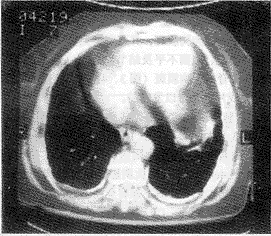

1.2.1 胸膜改变:X线片可观察到胸膜改变5例,其中1例疑为胸膜斑。CT检查发现胸膜改变高达16例,其中6例为胸膜斑,并可观察到胸膜斑钙化、小块的胸膜斑、表面不平及结节状表现(图1、2、3),还有3例脊椎旁胸膜斑(图3、4)。CT检查所见的改变在X线片上是难以发现的。

患者接触石棉9年(1956~1965年)

图3 双后侧胸膜斑,包括双侧脊椎旁胸膜斑